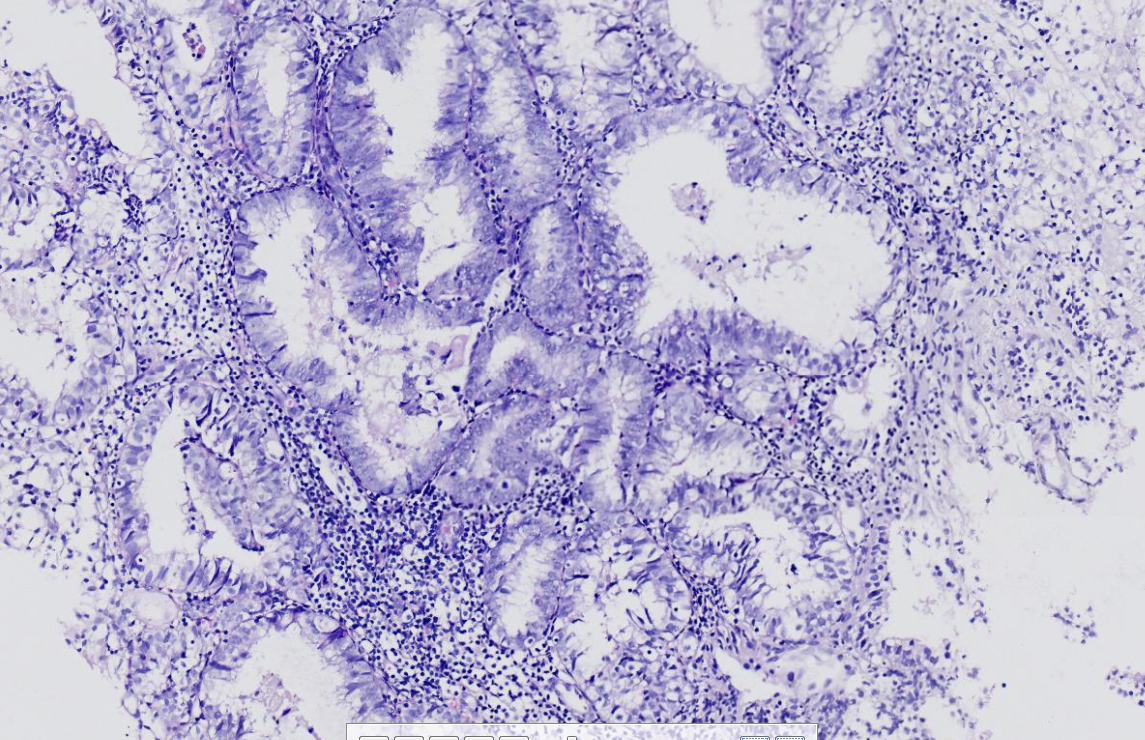

性别

女

年龄

62岁

不规则出血半年

子宫内膜(刮宫)

灰红软组织一堆,体积0.5*0.4*0.3cm。

临床情况:月经史?之前有无诊刮及诊断?有无用药?内膜呈高分泌相改变,部分腺体呈非典型增生改变。

非典型性子宫内膜增生。